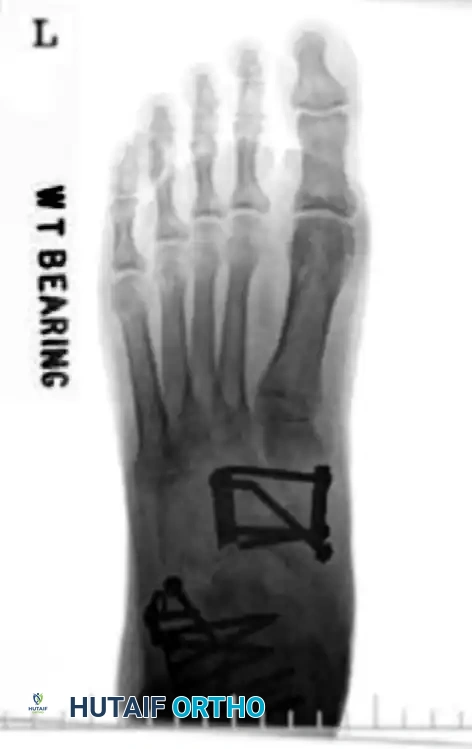

Clinical Evaluation and Radiographic Parameters

Any injury resulting in midfoot tenderness, swelling, or an inability to bear weight merits rigorous evaluation.

Radiographic Evaluation:

Standard non-weight-bearing radiographs often miss subtle instability. Weight-bearing radiographs are absolute requirements if the patient can tolerate them. If the patient cannot bear weight, a short-leg cast should be applied for 10-14 days, followed by repeat weight-bearing films.

Key radiographic parameters to evaluate:

1. The medial shaft of the 2nd metatarsal must align perfectly with the medial aspect of the middle cuneiform on the AP view.

2. The medial shaft of the 4th metatarsal must align perfectly with the medial aspect of the cuboid on the oblique view.

3. The 1st metatarsal-cuneiform articulation must show no incongruency.

4. The "Fleck Sign": Look for a small bony avulsion in the space between the medial cuneiform and the base of the 2nd metatarsal. This represents a bony avulsion of the Lisfranc ligament.

5. Evaluate the naviculocuneiform articulation for subtle subluxation.